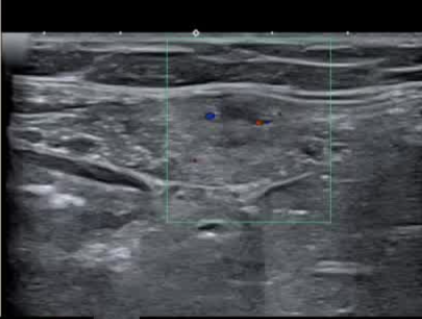

影像引导方式:超声和横断面成像(CT或MRI)结合是最常用的影像引导方式(10/16,62.5%)。

保护措施:几乎所有干预都需要辅助保护措施,其中水分离术(13/16,81.3%)和水分离术与温盐水填充手套的皮肤保护结合(9/16,56.3%)是最常见的保护措施。

通常需要三根布针